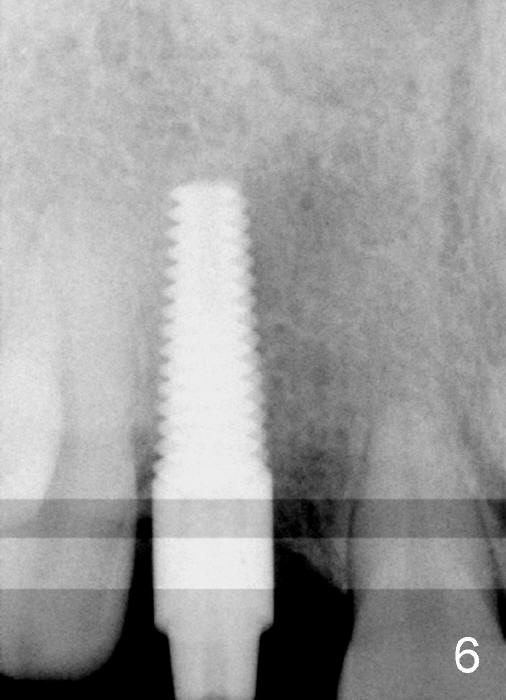

Malpositioned implant in the anterior region is cosmetically unacceptable. Immediate provisional allows us to note the issue immediately. The crown looks too long. Secondly, the provisional is easily dislodged, since the buccal aspect of the angled abutment is over trimmed (Fig.1). The implant (3.8x14 mm), which has been placed 3.5 months, is unexpectedly easily removed by reverse torque (Fig.2). The buccal wall is intact, whereas there seems to be enough bone lingually to place an implant. A small incision is made (Fig.11) so that the gingival tissue can be transferred buccally (Fig.12) and the immediate implant is to be placed palatally (Fig.13 white circle). There is no difficulty forming osteotomy in the palatal wall, followed by inserting 4.5x20 mm tap at the depth of 17 mm (Fig.3,5). But the tap is not palatal enough (Fig.4). By removing more palatal bone, the 4.5x17 implant (Fig.6) appears to be placed palatally enough for restoration (Fig.7; A: abutment; *: buccal gap). The biggest problem is that the palatal flap (Fig.7 arrowheads) cannot be pushed buccally; instead remains palatally. This leads to buccal tissue deficiency (Fig.8). Connective tissue graft is offered, but declined. The patient insists that she has low smile line. Following immediate provisional, mixture of allograft and synthetic graft is placed in the buccal gap (Fig.9). The overbuilt graft is held in place by perio dressing.